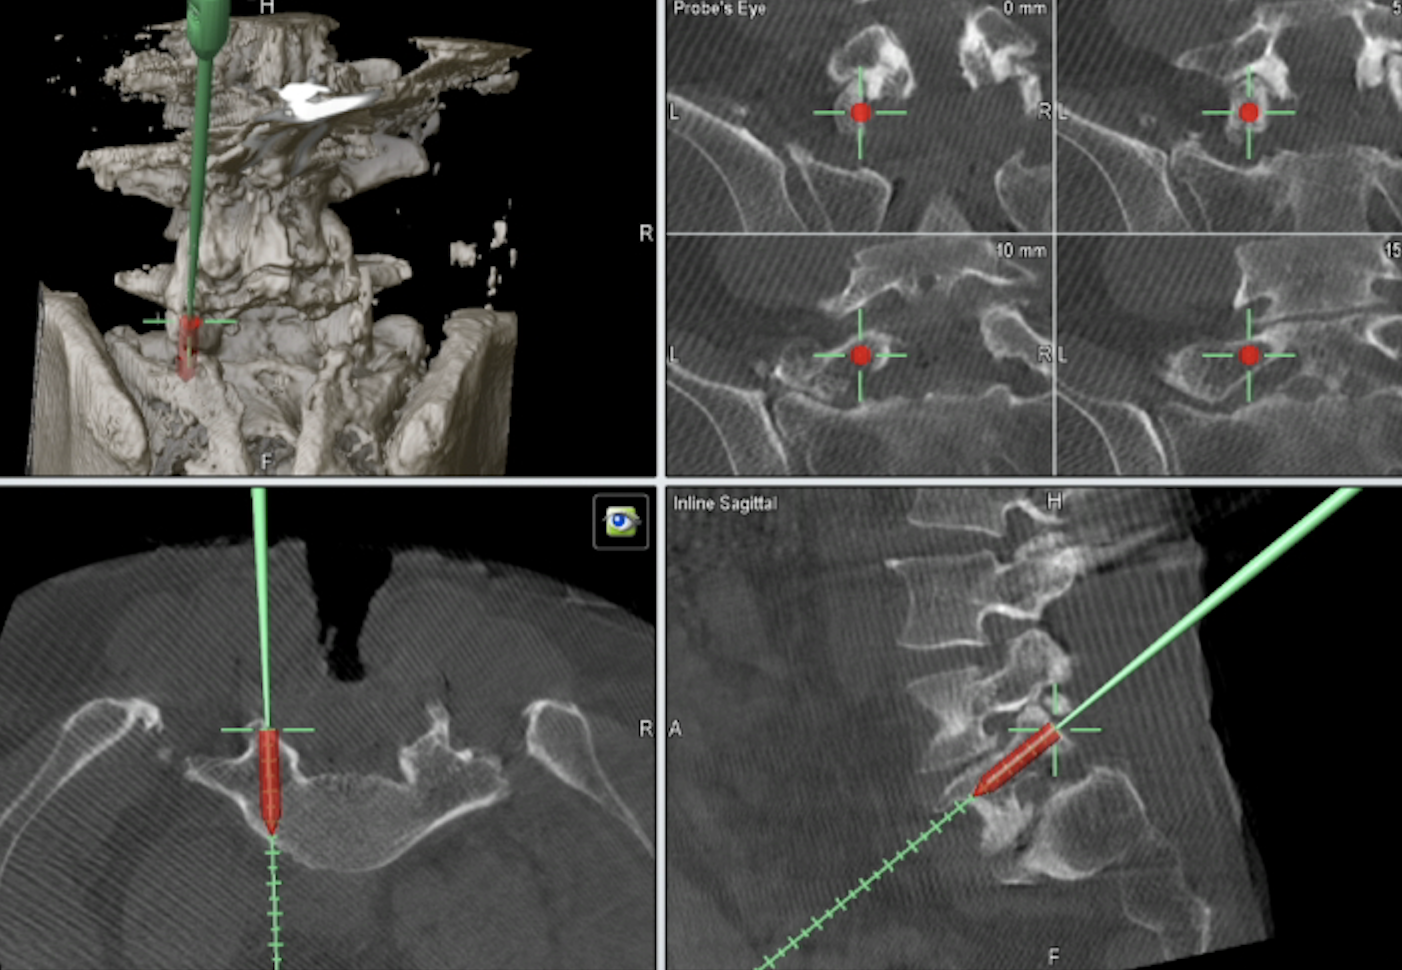

脊椎脊髄の手術 脊椎脊髄外傷 | 町田の脳神経外科・脊髄外科・神経内科「町田脳神経外科」

「脊椎脊髄の手術」平林 洌 / 長島 親男 / 戸山 芳昭 / 阿部 俊昭定価: ¥ 20000マーカー少しあり#平林洌 #平林_洌 #長島親男 #長島_親男 #戸山芳昭 #戸山_芳昭 #阿部俊昭 #阿部_俊昭 #本 #自然/医療・薬学・健康